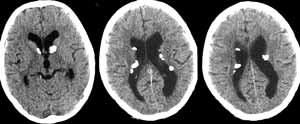

Больной К. 9 лет. Жалобы на наличие миоклонических судорожных припадков, задержку психоречевого развития. Кожа бледно-розовая, на лице, руках — туберозные бугорки. Печень +2 см, селезенка не пальпируется; в правой половине живота определяется образование. По данным РКТ головного мозга обнаружены субэпендимальные кальцинаты с четкими контурами и признаки внутренней гидроцефалии (Рис. 1). При проведении РКТ и УЗИ почек визуализируются двусторонние солидные опухоли размером до 82х90х126мм. (ангиомиолипома — по данным гистологического исследования). (Данные исследования предоставлены Республиканским научно-исследовательским цетром детской онкологии и гематологии; РК-томограф Tomoscan SR (Philips).

[Увеличить]

Рис. 1. РК-томограммы головного мозга. Визуализируются мультифокальные очаги высокой плотности, расположенные субэпиндимально.